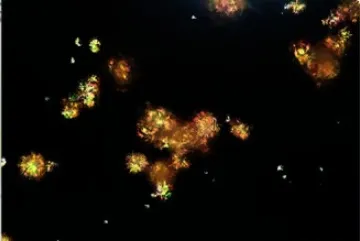

Devido à persistência da cristalúria de ácido úrico, foi solicitada uma revisão manual do sedimento urinário por um observador experiente, que identificou a seguinte imagem:

Na análise urinária os cristais apresentavam formato esférico irregular e estrias radiais, coloração amarela a marrom e forte birrefringência positiva. Com suspeita clínica de IRA associada a cristais de SMX, foi realizada a alcalinização da urina com bicarbonato de sódio. O paciente respondeu favoravelmente, com resolução completa da IRA.